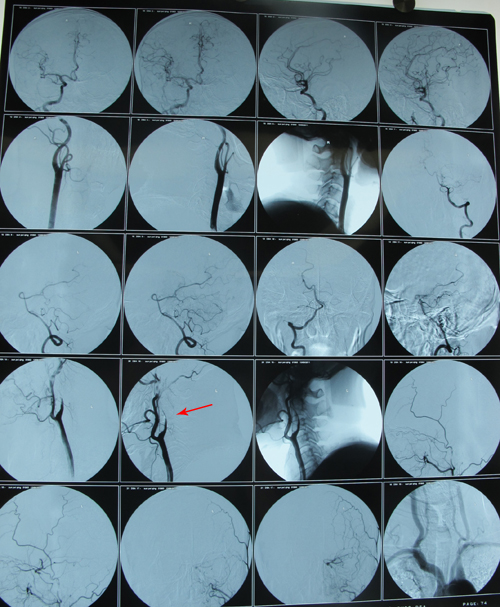

DSA示:左侧颈内动脉闭塞。

2011年6月23日,协作组张勤奕教授应邀前往同煤总医院为该患者实施颈动脉内膜剥脱术。术中从患者的左侧颈内动脉剥除大量血栓,但是远端无法再通,遂实施颈内动脉残根切除术。